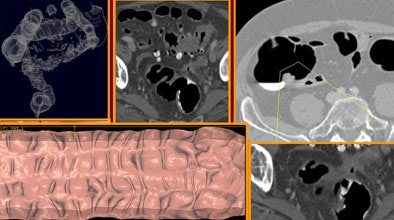

![]() |

| In an 85-year-old man suffering from severe abdominal pain and anemia, the colonoscope was stopped at the sigmoid colon due to severe diverticular disease. But VC showed no polyps or masses. All images courtesy of Dr. Franco Iafrate. |